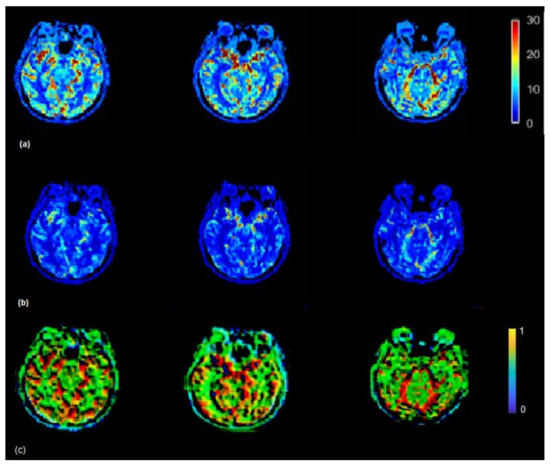

The CBF brain map was generated in the absence of scaling of AIF as well as by using the VOF rescaling approaches (Figure 5). In some cases, relative to the CBF map generated by using non-rescaled AIF, the CBF map generated by rescaled AIF approaches showed increased CBF values on the slices in the left and right hemispheres (red color) (visible in Figure 5). From Equations (5) and (6), it follows that the ratio of scaled and unscaled CBF values should be the scaling factor k. The images of the ratio of scaled and unscaled maps are expected to show the factor k for every voxel (Figure 5c). The mean CBF values, based on all 15 subjects using non-rescaled (AIF ROI width = 5 voxels) and VOF approach, were 43.98 and 61.16 mL/100g/min, respectively. The mean CBF values for AIF-rescaled and peak scaled approach were 57.10 and 47.10 mL/100g/min, respectively. At individual level, all the fifteen patients in this study did not follow similar pattern of underestimated CBF values due to the PVE. This has been demonstrated by studying the association of increasing degree of the PVE with deviation of CBF (Supplementary Material, Figure S1). To generalize, we need a larger dataset to conclude whether the scaling corrects the underestimation of CBF, as this could vary patient to patient in a small cohort.

Figure 5.

(a) CBF (mL/100 g/min) map generated by using rescaled AIF (b) and non-rescaled AIF (bottom). CBF map generated using rescaled AIF represents increased CBF values in the shown axial brain slices. CBF maps from non-rescaled AIF display mostly all the ROIs with decreased blood flow which makes it difficult to locate the regions which actually have a decreased flow. CBF images derived using rescaled AIF display ROIs with increased flow (red color) which helps to segregate the regions with decreased blood flow. This may help clinicals to identify the infract regions as well as regions with decreased blood flow on visual brain CBF images. (c) Maps illustrating the ratio between CBF values derived from the scaled and the non-scaled AIF.